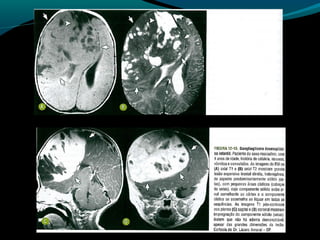

Glioblastoma

Maligno;

Origem astrocítica;

Grau IV;

60% dos astrocitomas;

15% das neoplasias intracranianas;

Mais frequente em adultos;

Sobrevida de 9 a 12 meses;

TC:

Geralmente supratentorial;

Infiltra substância branca;

Processo expansivo iso ou hipodenso de limites mal

definidos e necrose central;

Pode apresentar hemorragias;

Calcificações são raras;

RM:

Sinal heterogêneo em T1, T2 e FLAIR; (necrose, cistos,

hemorragia, neovascularização); mas predomina

hipointensidade em T1 e hiper em T2 e FLAIR;

Realce difuso e heterogêneo pelo Gd;